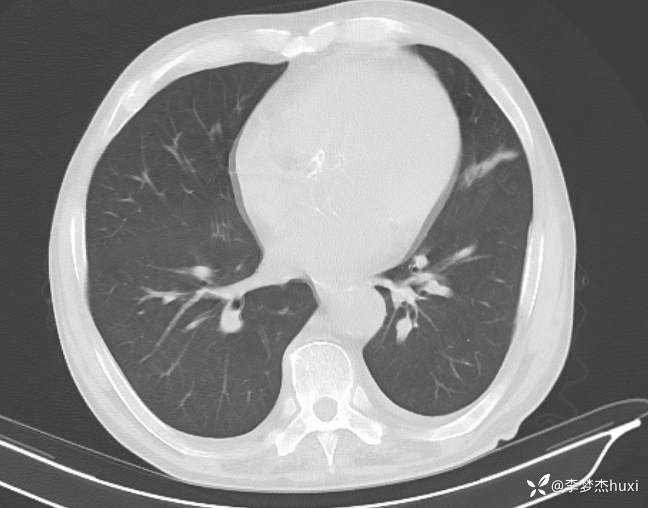

【现病史及既往史】: 1.现病史:患者老年 男,患者缘于入院前4天无明显诱因出现发热,体温最高达39.5℃,偶有咳嗽,伴少量咳痰,为白痰,伴胸闷、憋气,伴喘息,活动后明显,伴腹部胀满,伴呃逆,发热时伴头痛,无头晕,伴周身乏力,无咯血,无鼻塞、流涕,无恶心、呕吐,无腹痛、腹泻,无尿频、尿急、尿痛,无血尿,院外肌注药物治疗(具体不详),发热呈反复性,遂就诊于我院门诊查胸部CT:考虑左肺上叶炎症,双肺纹理增重,主动脉管壁钙化,冠状动脉钙化,双侧胸膜增厚,脾脏增大,肝脏及脾脏周围少量积液。血常规:白细胞数目31.07x109/L,淋巴细胞百分比8.2%,中性粒细胞百分比83.4%,单核细胞数目1.47x109/L,中性粒细胞数目25.93x109/L,红细胞数目2.03x1012/L,血红蛋白67g/L。C-反应蛋白25.47mg/L;SAA152.93mg/L。门诊以“感染性发热”收住院。

【临床诊断】:感染性发热